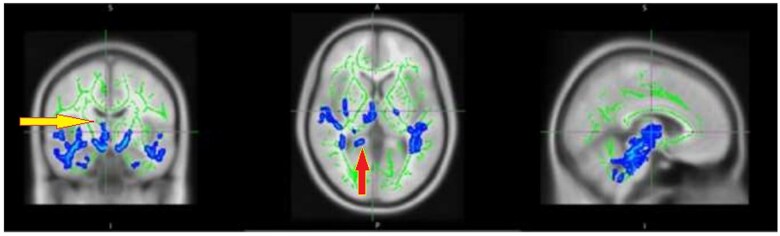

Methods: A prospective cohort analysis was conducted comprised 60 RA patients with fatigue, categorized into active (n = 30) and non-active (n = 30) disease states, alongside 20 healthy controls (HC). A 3 Tesla MRI system was utilized to perform diffusion tensor imaging (DTI) and magnetization transfer imaging (MTI) sequences. MTR maps were generated using in-house MATLAB code and co-registered with DTI data using SPM8. These were then analyzed through tract-based spatial statistics (TBSS) with threshold-free cluster enhancement (TFCE) and corrected for multiple comparisons. MTR values were assessed using Randomize from the FSL toolkit, applying a general linear model (GLM) for voxel-wise analysis and TFCE for p-value generation, with family-wise error (FWE) control (P < .05) for multiple comparisons.

Results: The RF group exhibited significantly lower myelin integrity (TFCE, P < .05) compared to HCs, particularly in the middle cerebellar peduncle and splenium of the corpus callosum, with no marked difference between active and non-active RA disease statuses. There is a discernible disparity in myelin integrity between RA patients with fatigue and healthy individuals, suggesting microstructural white matter alterations that are congruent with DTI findings.

Conclusion: This study reveals that rheumatoid arthritis (RA) patients with fatigue exhibit significantly lower myelin integrity, particularly in the middle cerebellar peduncle and splenium of the corpus callosum, compared to healthy controls. Notably, this finding was consistent regardless of the active or non-active status of the RA disease, highlighting persistent white matter alterations in this patents cohort.